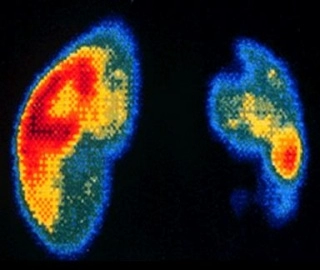

Сцинтиграфия почек

Сцинтиграфия почек применяется в урологии для выявления патологии тканей мочевыделительной системы. В организм пациента внедряют радиофармацевтический раствор, а затем отслеживают при помощи 3D рентген-установки его прохождение через систему мочевыделения.

Высокоинформативная методика позволяет обнаруживать на ранних стадиях и диагностировать дисфункцию почек, воспалительные процессы, опухоли, камни и другие изменения.

Нефросцинтиграфия — это радиоактивное исследование, которое показывает функциональные изменения почек и мочевыводящих путей. Процедура совершенно безопасна и безболезненна, поэтому показана даже детям раннего возраста. Для выполнения исследований используются меченные короткоживущим изотопом Тс-99м препараты. Они быстро выводятся из организма. Благодаря короткому периоду полураспада изотопа, облучение пациента незначительно и находится в регламентирующих пределах.

Статическая нефросцинтиграфия Метод исследования почек, позволяющий оценить их анатомо-топографических особенностей и функциональное состояние паренхимы почек. В процессе исследования определяется форма, размеры, положение почек, а также локализация, распространенность и степень выраженности патологического процесса. Кроме того, данная методика позволяет оценить жизнеспособность почечной ткани, наличие и степень выраженности рубцовых процессов при различных заболеваниях почек.